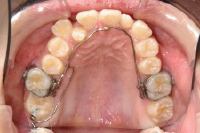

矯正治療計画に基づき、その治療達成のための方法(=矯正装置)が決まりましたら、いよいよその装置を制作します。矯正装置には自分で取り外せる装置(=可撤式装置)と自分で取り外せない装置(=固定式装置)とがあります。一回でできるケースもありますが、多くは何度かの通院で制作します。

上顎の内側に装置

上顎の外側にセラミックブラケットを装着

下顎の奥歯にバンドを装着

下顎の外側にセラミックブラケットを装着

矯正治療中の来院は通常月約一回ですが、装置を作成しているときは、月に二回以上回来院していただくこともあります。